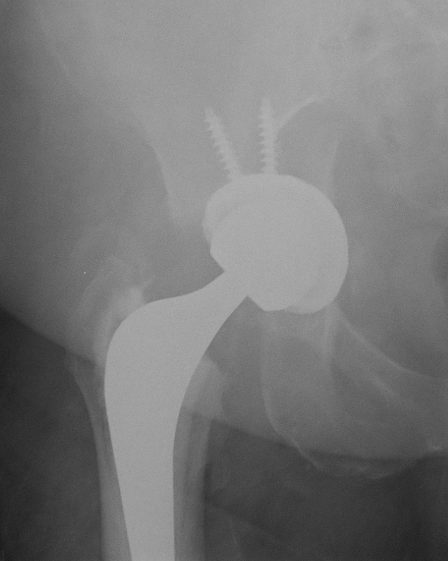

Screw fixation

Goal

Transacetabular screw fixation to augment initial cup stability

Safe zones

- anatomical cadaveric study

- line ASIS to to ischial tuberosity through center of acetabulum

- line perpendicular to this creates four quadrants

- safe quadrants are the posterior quadrants

- anterior screws can emerge within pelvis

PS quadrant

- sciatic nerve / superior gluteal nerve and vessels in danger at greater sciatic notch

- aim screw between 2 cortices of ilium

- direct towards sacro-iliac joint

- can tolerate 85 mm screws